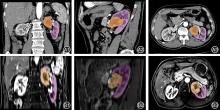

目的 分析3D数字化全息影像及术中导航技术在腹腔镜肾部分切除术中应用的可行性与有效性。 方法 选取2023年6月至2025年1月就诊于合肥市第二人民医院泌尿外科行腹腔镜肾部分切除术的46例患者为研究对象,随机分为观察组和对照组,观察组23例患者术前采用3D数字化全息影像重建进行术前规划和术中行实时导航。对照组23例患者术前采用最佳参数的二维影像(增强CT与增强MRI)进行术前规划。比较两组患者术前资料(性别、年龄、体质量指数、肿瘤直径、Renal评分)、术中指标(手术总时间、热缺血时间、术中出血量、血红蛋白变化值、术后住院时间、拔除引流管时间),肾功能变化指标(术前与术后1个月血肌酐变化值、术前与术后1个月肾小球滤过率变化值)及术中(肾集合系统损伤)和术后并发症(切缘阳性率、出血、皮下气肿、尿瘘)等发生率。 结果 成功构建了观察组23例肾肿瘤患者的全息影像,并对各个组织进行不同颜色标记,术前可直观地展示肾脏及肿瘤病灶、集合系统、肾动静脉、肾上腺、下腔静脉等组织并进行术前规划,术中提供实时的空间引导,精准定位肿瘤并辅助切除。对照组23例患者均采集到最佳参数的增强CT与增强MRI图像进行术前规划。本研究46例患者均由同一名具备相应资质的主刀医师实施腹腔镜肾部分切除术,术后病理均为肾肿瘤,其中透明细胞癌(27例)、嫌色细胞癌(7例)、乳头状细胞癌(5例)、肉瘤样癌(2例)和血管平滑肌脂肪瘤(5例),两组患者一般临床资料比较,组间差异无统计学意义(P > 0.05),观察组的手术时间、热缺血时间、出血量、血红蛋白变化及术后1个月肌酐变化均显著优于对照组(P < 0.01),观察组术后住院时间、拔除引流管时间、术前与术后1个月肾小球滤过率变化值小于对照组,差异无统计学意义(P = 0.175、0.331、0.273)。观察组与对照组均未发生术中并发症,未损伤集合系统,对照组术后切缘阳性1例,出血1例,皮下气肿1例,差异无统计学意义(P > 0.05)。 结论 基于MRI与CT数据融合的3D数字化全息影像及术中导航技术有助于术前规划和术中精确导航,在确保疗效的同时,可以减少手术时间,保护肾脏功能,降低围术期风险。

Objective To evaluate the feasibility and effectiveness of 3D digital holographic imaging combined with intraoperative navigation technology in the context of partial nephrectomy. Methods A total of 46 patients who underwent laparoscopic partial nephrectomy in the Department of Urology at the Second People's Hospital of Hefei City between June 2023 and January 2025 were randomly assigned to either the experimental group or the control group. The experimental group (n = 23) utilized preoperative planning and intraoperative real-time navigation based on 3D digital holographic imaging, whereas the control group (n = 23) relied on preoperative planning using optimized two-dimensional images obtained via contrast-enhanced CT and MRI scans. Preoperative data—including gender, age, body mass index (BMI), tumor diameter, and RENAL score—were collected. Intraoperative parameters such as total operative time, warm ischemia time, intraoperative blood loss, hemoglobin levels, postoperative hospitalization duration, and time to drain removal were recorded. Renal function changes were assessed by comparing serum creatinine levels and estimated glomerular filtration rates (eGFR) before surgery and one month post-surgery. Additionally, the incidence of intraoperative complications—particularly injury to the renal collecting system—and postoperative complications—including positive surgical margins, bleeding, subcutaneous emphysema, and urinary fistula—was analyzed. Results In this study, holographic images were successfully reconstructed for 23 patients with renal tumors in the experimental group. Each anatomical structure—including the kidney and tumor lesions, collecting system, renal arteries and veins, adrenal glands, and inferior vena cava—was color-coded to enable intuitive visualization. These images were used for preoperative planning and provided real-time spatial orientation to accurately locate and guide resection of the tumor during surgery. In the control group, 23 patients underwent preoperative planning based on contrast-enhanced CT and MRI scans acquired using optimized parameters. All 46 patients underwent laparoscopic partial nephrectomy performed by the same qualified surgeon, and postoperative pathological analysis confirmed renal tumors, including 27 cases of clear cell carcinoma, 7 cases of chromophobe cell carcinoma, 5 cases of papillary cell carcinoma, 2 cases of sarcomatoid carcinoma, and 5 cases of angiomyolipoma. No significant differences were observed in baseline clinical characteristics (including age, body mass index, tumor diameter, and RENAL score) between the two groups (P > 0.05). The experimental group showed significantly lower values in total operative time, warm ischemia time, intraoperative blood loss, pre- to postoperative hemoglobin changes, and pre-surgical to one-month post-surgical creatinine changes compared to the control group (P < 0.01). Additionally, the experimental group exhibited smaller changes in hospitalization duration, time to drain removal, and glomerular filtration rate from preoperative to one month post-surgery; however, these differences were not statistically significant (P = 0.175, P = 0.331, and P = 0.273). There were no intraoperative complications or damage to the collecting system in either the experimental or control groups. Postoperatively, the control group experienced one case of positive surgical margin, one case of hemorrhage, and one case of subcutaneous emphysema. No statistically significant differences were observed between the groups (P > 0.05). Conclusions 3D digital holographic imaging combined with intraoperative navigation technology, based on the fusion of MRI and CT data, facilitates preoperative planning and precise intraoperative guidance. This approach helps reduce operative time, preserve renal function, and lower perioperative risks while ensuring therapeutic efficacy.